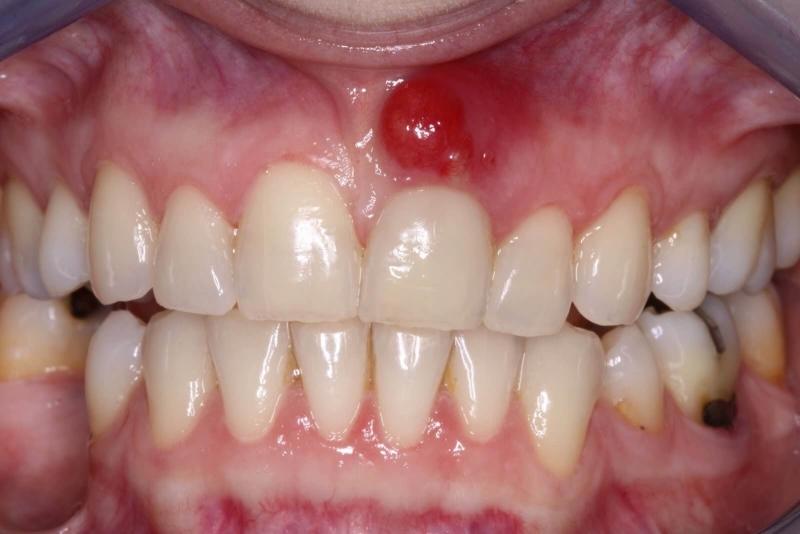

Основной причиной появления нароста на десне (см. фото) является попадание гнилостных бактерий в мягкие ткани. Существует множество факторов, способствующих образованию наростов, но можно выделить основные из них:

Врачи отмечают, что нарост на десне может быть признаком различных стоматологических заболеваний. Чаще всего такие образования возникают из-за воспалительных процессов, таких как гингивит или периодонтит. Специалисты подчеркивают, что игнорировать подобные симптомы не стоит, так как они могут привести к более серьезным проблемам, включая потерю зубов. Важно своевременно обратиться к стоматологу для диагностики и лечения. В некоторых случаях нарост может быть доброкачественным, но в других — требовать более тщательного обследования, чтобы исключить онкологические заболевания. Регулярные профилактические осмотры помогут избежать осложнений и сохранить здоровье полости рта.

На первичном осмотре врач обращает внимание на состояние десен, зубов и окружающих тканей. Важно провести визуальную оценку нароста: он может быть гладким или шероховатым, мягким или твердым, подвижным или фиксированным. Эти характеристики могут дать важные подсказки о природе образования.